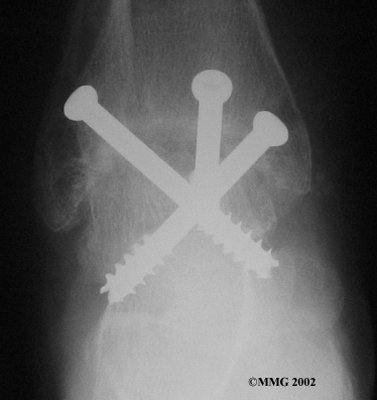

It is important when the surfaces are removed that the angles of the cut surfaces are correct. When the tibia is brought against the talus, the foot should be at a right angle to the lower leg. Once the cuts are made the bones must be held in place while they fuse. This can be done using large metal screws and metal plates if necessary. The screws are usually under the skin and are not removed unless they begin to rub and cause pain.

Inserting the screws

After ankle fusion, the physical therapists at FYZICAL Gainesville Central can help you learn to walk smoothly and without a limp. Although time needed for recovery varies among patients, an ankle brace will typically replace your cast after eight to 12 weeks. Your surgeon will take X-rays frequently to see if the bones are fusing together. You will probably need to use crutches during the time you wear the cast. As the fusion grows stronger, you will begin to put more weight on your foot when walking.